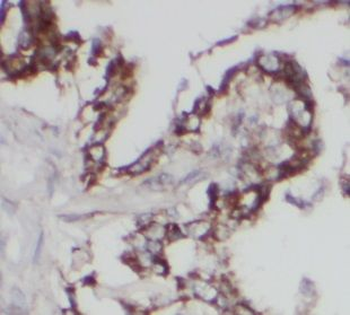

应用稀释比例:WB: 1:500-1:2000; IHC: 1:20-1:200; IP: 1:20O-1:1000

Immunohistochemistry of paraffin-embedded human lung cancer using orb632363 (UGCG antibody) at dilution of 1:100.